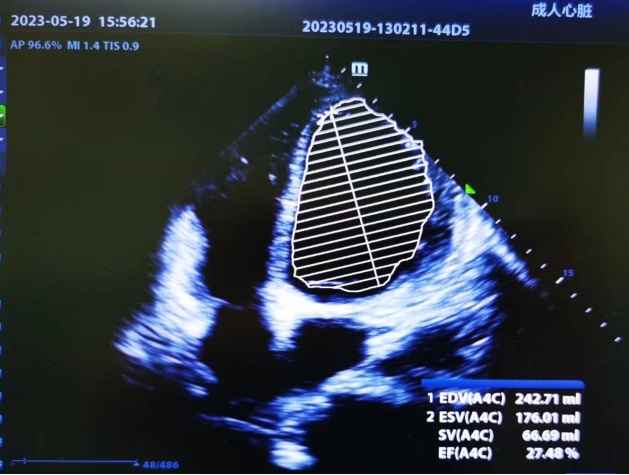

手术结束时的超声监测

“喂,吴主任吗,我这儿有位80岁老伯,他下体腹股沟出现巨大疝气,但他的情况很特殊,不太好上麻醉………”5月中旬的一天,接诊吴老伯的区中心医院普外科主任张俊华,第一时间联系了麻醉科主任吴德华。原来,老人因患有腹股沟斜疝已严重影响日常行走及生活,但10年前其做过心脏手术,目前心脏超声检查显示其整个心脏扩大,心脏收缩功能极度受损,甚至部分心脏肌肉无法正常收缩。如果麻醉方法和术中处理有任何的失误,都可能引发心脏收缩能力进一步下降,甚至出现严重心律失常以及心跳突然停止,威胁生命。不仅如此,老人还患有肾功能衰竭,这些都给手术麻醉带来不小的风险。